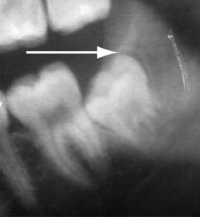

Segment of an orthopantomogram showing an impacted wisdom tooth: a radiolucent area (arrow) is seen behind an impacted right lower wisdom tooth from a patient with pericoronitis.

Ideal management: Pericoronitis should be treated by irrigation of the pericoronal space with a sterile solution such as saline or 0.12% chlorhexidine. Broad spectrum antibiotics should be given if there are systemic symptoms.7,8 The patient should be referred to an oral and maxillofacial surgeon/dentist for surgical extraction of the tooth.